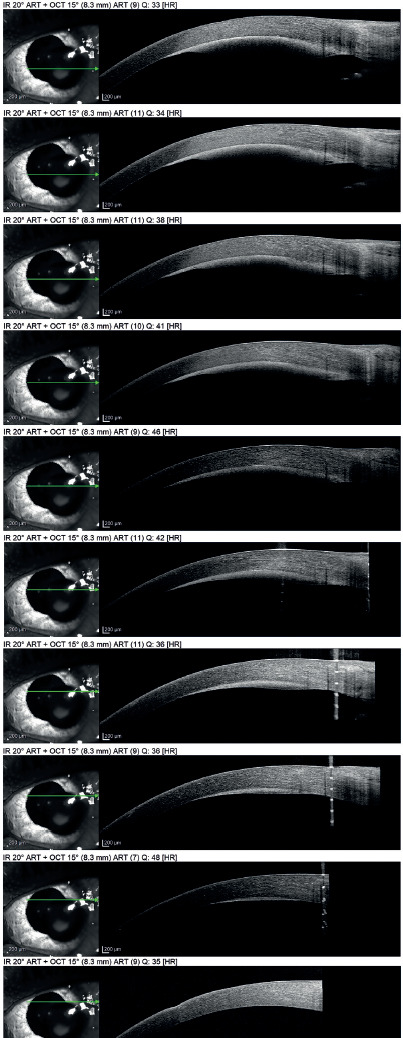

Day 1 examination revealed a dark red, rounded drop of blood in the supertemporal quadrant of the cornea in the sub- Descemet plane (between the corneal stroma and the Descemet membrane), not encroaching on the pupil border (Figure 1). An Anterior segment optical coherence tomography (AS-OCT) confirmed the location of the blood (Figure 2). The BCVA was still HM (the same as preoperatively), the bleb was pale, diffuse, and low, and the fundus demonstrated flat retina and flat choroidals with a C/D ratio of 0.9 (as preoperatively). The patient was instructed to instill the postoperative topical medications and maintain follow-up. Subsequent follow-ups over several months revealed gradual depigmentation of the sub-Descemet blood transforming into a yellow colour while retaining the same size (Figure 1). After 1 year of follow-up examination revealed a BCVA of 0.5 (OD) and 0.12 (OS), a manifest refraction of cylinder –0.75 × 95° (OD) and –6.0 cyl –4.0 × 115° an IOP of 12 mmHg (OD) and 10 mmHg (OS), clear lenses, cup/ disc ratios of 0.5 (OD) and 0.9 (OS) and a pale, diffuse, low bleb (OS). The localised sub-Descemet haemosiderin deposit remained stationary until the final follow-up.

Figure 1

Composite demonstrating the slit lamp photos of the operated eye. The top row demonstrates the appearance of the eye on day 1 postoperatively. A) Diffuse illumination photo demonstrating localised haemorrhagic Descemet detachment. B) Diffuse illumination photo with the eye looking down, demonstrating the operative site and the early filtering bleb. C) Optical section photo demonstrating the sub-Descemet location of the localised haemorrhage. Middle row demonstrating the appearance of the eye 5 months postoperatively. D) Diffuse illumination photo demonstrating localised haemorrhagic Descemet detachment with starting a localised area of haemoglobin breakdown into haemosiderin with evident localised colour change. E) Optical section photo demonstrating the sub-Descemet location of the localised haemorrhage with the area of haemosiderin in the centre. F) Oblique illumination photo with the eye looking down, demonstrating the operative site and the filtering bleb. Bottom row demonstrating the appearance of the eye 1 year postoperatively. G) Diffuse illumination photo demonstrating localised lesion of haemosiderin deposited beneath the Descemet detachment. H) Optical section photo demonstrating the sub-Descemet location of the localised haemosiderin deposit. I) Oblique illumination photo with the eye looking down, demonstrating the operative site and the filtering bleb